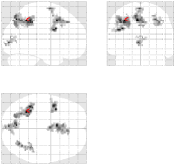

Fig. 8 reports on the robustness of the proposed pMRI pipeline to the between-subject variability for this motor contrast. Since sensory functions are expected to generate larger BOLD effects (higher SNR) and appear more stable, our comparison takes place at . Two subject-level Student’s -maps reconstructed using the different pMRI algorithms are compared in Fig. 8. For the second subject, one can observe that the mSENSE algorithm fails to detect any activation cluster in the right motor cortex. By contrast, our 4D-UWR-SENSE method retrieves more coherent activity for this second subject in the expected region.

| mSENSE | UWR-SENSE | 4D-UWR-SENSE | |

|---|---|---|---|

| Subj. 1 |  |

|

|

| Subj. 5 |  |

|

|